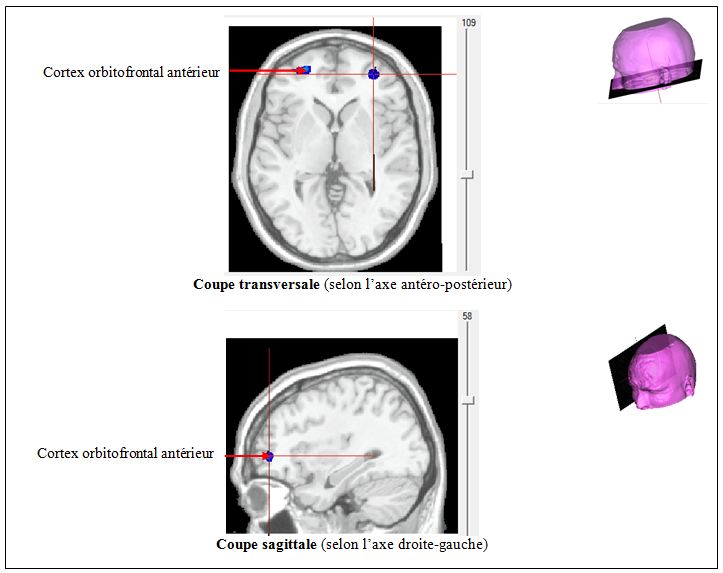

Argent sup Erotique